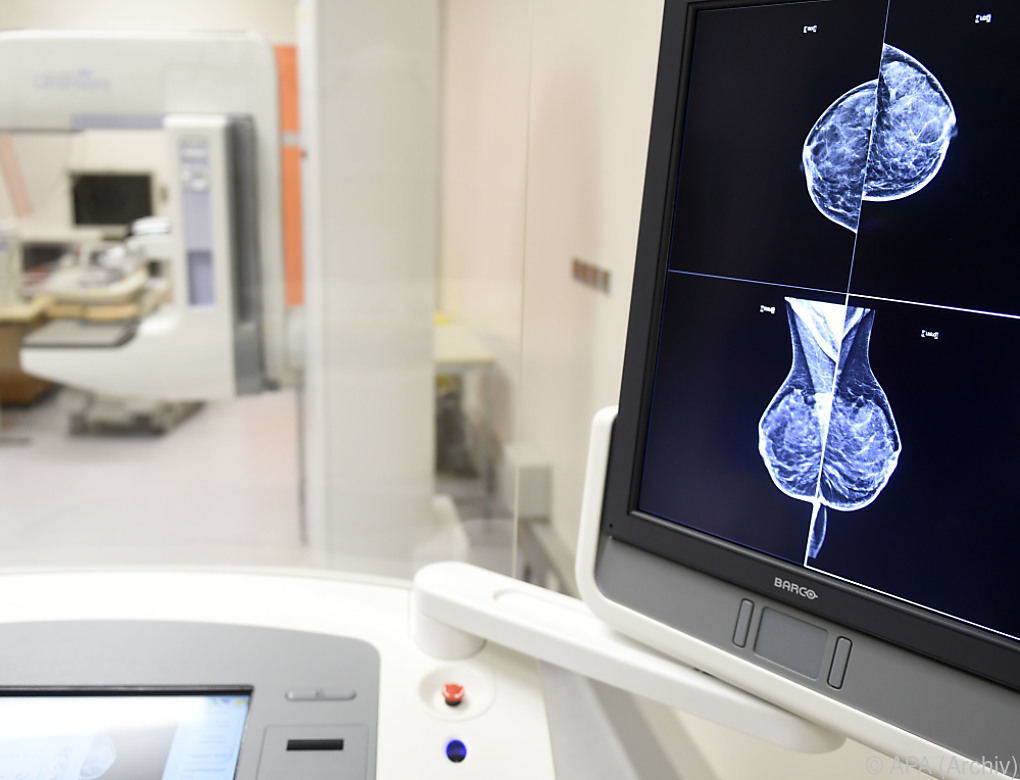

Die Geschichte reicht bis in den Herbst 2018 zurück. Bei einer Routineuntersuchung wurden damals verdächtige Mikroverkalkungen in der Brust festgestellt, die eine eingehendere diagnostische Abklärung erforderten. Die Patientin unterzog sich daraufhin einer Mammabiopsie. Die Entnahme der Proben erfolgte in den Ambulanzen der USL Euganea, während die histologische Untersuchung in den Labors des Krankenhausverbunds durchgeführt wurde. Das Ergebnis lautete „infiltratives duktales Karzinom dritten Grades“ – eine aggressiv und fortgeschritten geltende Form des Brustkrebses, die einen sofortigen Eingriff erforderte. So wurde der Frau am 21. November desselben Jahres in einer Klinik in Abano Terme die linke Brust vollständig entfernt.

Bei den gerichtsmedizinischen Untersuchungen fällt eine technische Unstimmigkeit ins Auge: Die Diskrepanz zwischen den 14 Gewebeproben, die bei der ursprünglichen Biopsie entnommen wurden, und den nur fünf Proben, die der Pathologe, der den Krebs diagnostiziert hatte, analysiert hatte. „Die Unstimmigkeit zwischen der Menge des bei der Biopsie entnommenen Materials und dem, was dem Pathologen zur Untersuchung vorgelegt wurde, ist offensichtlich”, betont Rechtsanwältin Da Ruos und verweist dabei auf die Analysen, die zum Antrag auf den Gentest führten.

Der endgültige Beweis ergab sich aus dem Vergleich der DNA der Frau mit dem seit 2018 aufbewahrten biologischen Material. Dieser DNA-Abgleich zeigte, dass die erkrankten Gewebe einer anderen Person gehören. Wahrscheinlich kam es zu einer Verwechslung des Gewebes. Doch wo? Während der Entnahme, der Identifizierung oder des Transports im Rahmen der Biopsieentnahmephase der USL Euganea? Oder während der Annahme und Bearbeitung im Histologielabor im Rahmen der diagnostischen Phase im Krankenhaus?